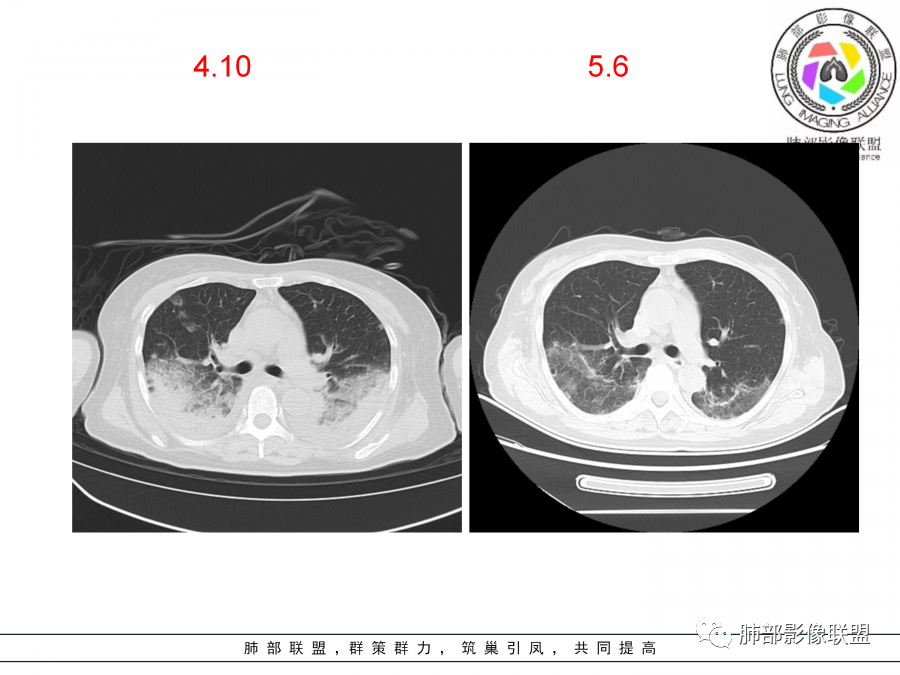

影像,第一次双肺中下叶胸膜下多发斑片状实变影,部分融合成,周围散发磨玻璃影,磨玻璃影内可见小叶间隔及小叶内间隔增厚,病变平行于胸膜,第二次间隔8天,双肺实变影明显进展,有重力作用,支气管近端堵塞,进展较快,临床有发热,血沉高,狼疮SLE阳性,考虑1:OP(机化性肺炎)2:SLE相关肺炎,建议支气管镜灌洗液病原学检测。

老年女性,咳嗽咳痰伴发热7天,白细胞不高,血沉快,降钙素原不高。其他化验未见明显异常,狼疮全套抗Ro/SSA阳性,双肺野靠近胸膜下磨玻璃实变影,支气管通畅,有充气征,沿胸膜下分布,有细网格征,7天后进展明显,实变影加重,胸膜肥厚,胸水不明显,心包少量积液?抗感染治疗无效,考虑非感染性疾病可能性大,结缔组织相关性肺病?狼疮性肺炎?机化性肺炎?鉴别病毒性肺炎。

老年女性,咳嗽咳痰发热7天。无气促。白细胞计数不高,PCT稍高,PPD(+),抗Ro/SSA阳性。CT:双肺野靠近胸膜下磨玻璃实变影,支气管通畅,有充气征,沿胸膜下分布,有细网格征。予抗生素治疗,8天后复查胸部CT见病灶范围扩大,实变影加重,胸膜肥厚,胸水不明显。抗感染治疗无效,考虑有:1.非感染性疾病:结缔组织相关性肺病,支持点:肺部CT表现为间质性炎症病变,抗RO/SSA(52)阳性;2.病毒性肺炎:患者无气促症状,可能性小;3.肺结核。

第一次双肺中下叶胸膜下多发斑片状磨玻璃及实变影,病变平行于胸膜,支气管通畅,8天后,双肺实变影明显进展范围扩大,部分支气管近端堵塞,进展较快,胸腔积液,抗感染治疗无效,考虑:非感染性疾病:结缔组织相关性肺病。鉴别机化性肺炎。

老年女性,咳嗽咳痰发热。PCT稍高,PPD(+),抗Ro/SSA阳性。CT:双下肺平行胸膜下实变影,支气管充气,有细网格征。一周抗炎复查病灶范围扩大,实变影加重,考虑结缔组织相关性肺病,sle_ss_ild?狼疮性肺炎?除外病毒性肺炎、肺结核。